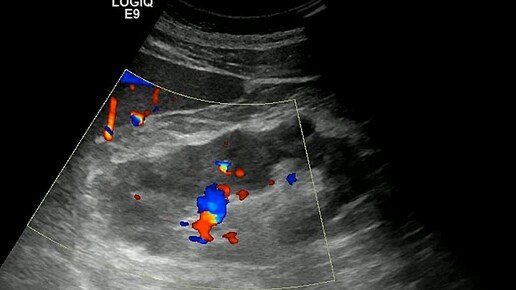

Ультразвуковые находки от врача УЗД Зорина Я.П.